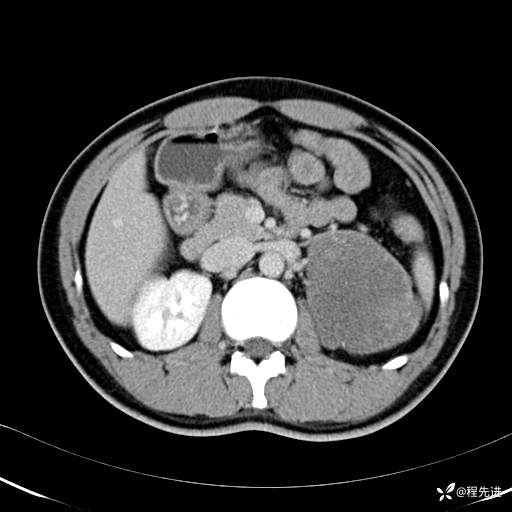

CT平扫:(CT值:平扫,27HU,动脉期,27HU,门静脉期,31HU,平衡期,32HU)

动脉期: